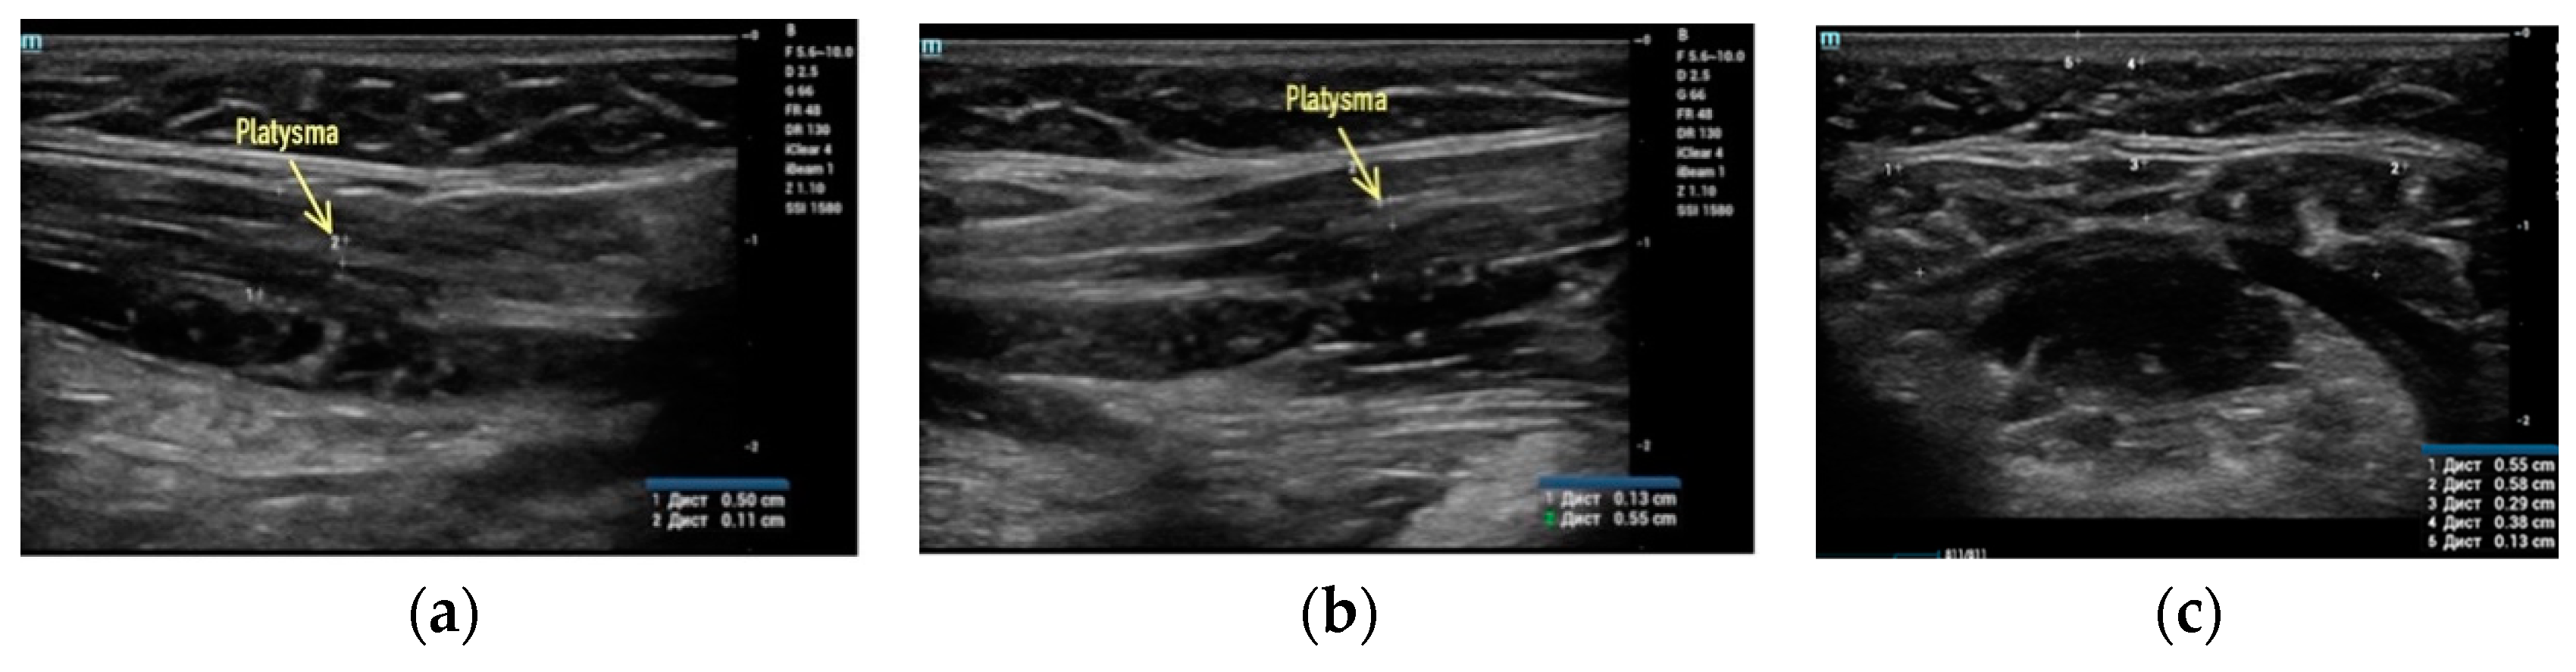

Clinical case #2. During the study, a 52-year-old female patient with a 15 MHz linear transducer of soft tissues of the lower third of the face and neck without pressure, in an upright position, displayed sagging platysma and the presence of cords on two sides (Figure 2a,b) as well as a slight accumulation of adipose tissue in the chin area (Figure 2c).

Figure 2.

B-mode ultrasound examination of the soft tissues of the lower third of the face and neck with a 14 MHz linear transducer. Sagging of the platysma, strands (a,b), and a slight accumulation of adipose tissue in the submental area (c).

According to the results of ultrasound examination, it is obvious that a radical improvement in the contours of the neck–submandibular angle will not be achieved by acting only on the adipose tissue; correction of ptotic platysma is also necessary in this clinical case.